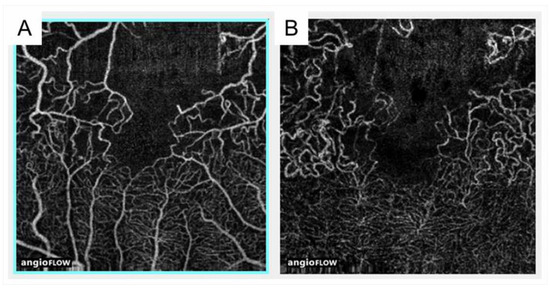

3.7. Collateral Vessels

- Suzuki, N.; Hirano, Y.; Tomiyasu, T.; Kurobe, R.; Yasuda, Y.; Esaki, Y.; Yasukawa, T.; Yoshida, M.; Ogura, Y. Collateral vessels on optical coherence tomography angiography in eyes with branch retinal vein occlusion. Br. J. Ophthalmol. 2019, 103, 1373–1379. [Google Scholar] [CrossRef] [PubMed]

- Tsuboi, K.; Sasajima, H.; Kamei, M. Collateral Vessels in Branch Retinal Vein Occlusion: Anatomic and Functional Analyses by OCT Angiography. Ophthalmol. Retina 2019, 3, 767–776. [Google Scholar] [CrossRef] [PubMed]

- Lee, H.E.; Wang, Y.; Fayed, A.E.; Fawzi, A.A. Exploring the relationship between collaterals and vessel density in retinal vein occlusions using optical coherence tomography angiography. PLoS ONE 2019, 14, e0215790. [Google Scholar] [CrossRef]

- Freund, K.B.; Sarraf, D.; Leong, B.C.S.; Garrity, S.T.; Vupparaboina, K.K.; Dansingani, K.K. Association of optical coherence tomography angiography of collaterals in retinal vein occlusion with major venous outflow through the deep vascular complex. JAMA Ophthalmol. 2018, 136, 1262–1270. [Google Scholar] [CrossRef] [PubMed]